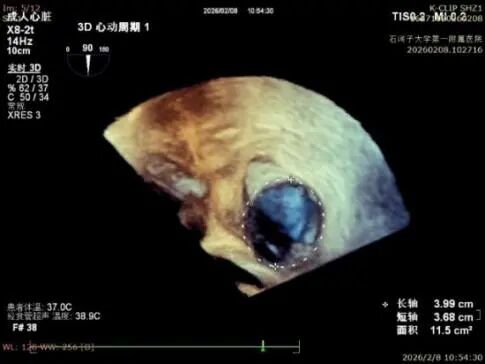

Echocardiographic Findings:Severe tricuspid regurgitation (4+; average vena contracta width, 12 mm). The regurgitation was predominantly anteroseptal and central, with a small posteroseptal component. During systole, the anterior and septal leaflets protruded slightly into the right atrium, with a protrusion height of 2.6 mm. A 6 mm gap was observed at the anteroseptal and central regions. Tricuspid annular dilatation was present (mean annular diameter, 40 mm), with a prominent gap at the anteroseptal region.

Preoperative 3D view of regurgitation

Preoperative annulus area: 11.5 cm²

Postoperative annulus area: 6.15 cm²